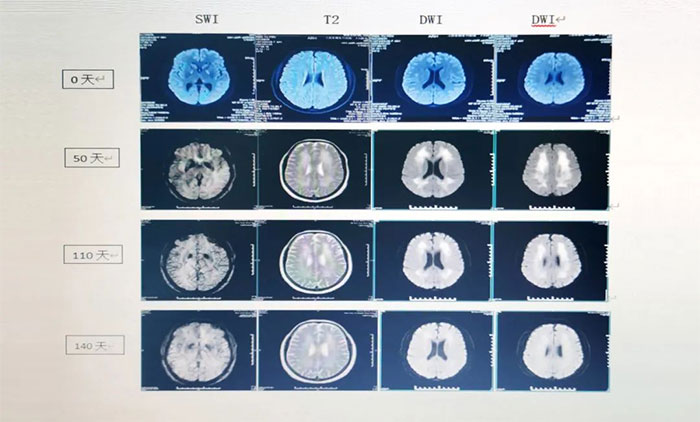

▲ ANE影像學(xué):具有多灶性、對(duì)稱性腦損害的特點(diǎn),病變內(nèi)出血和環(huán)形強(qiáng)化為經(jīng)典影像學(xué)表現(xiàn)。ADC加權(quán)像上呈特征性“同心圓結(jié)構(gòu)”。

▲ 患者影像變化

經(jīng)過會(huì)診,張靜波主任團(tuán)隊(duì)制定了完善的治療方案,給予靶向藥物托珠單抗及地塞米松治療,同時(shí)予繼續(xù)對(duì)癥及支持治療,以及高壓氧、經(jīng)顱磁刺激等治療。經(jīng)上述治療兩個(gè)月后,患者病情明顯好轉(zhuǎn),神志清晰,行走自如,可以正常與人交流,大小便也恢復(fù)正常,目前已經(jīng)康復(fù)出院。